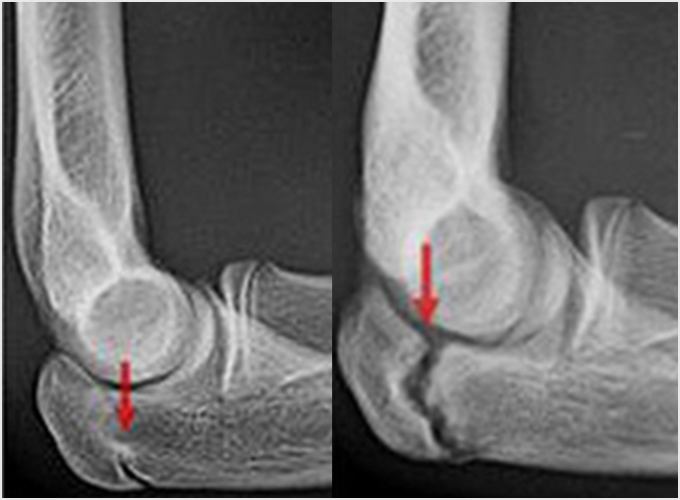

離断性骨軟骨炎(上腕骨小頭障害)

野球肘で最も重症になる障がいの1つです。ひどくなると関節軟骨の一部がはがれて関節ネズミとなったり、肘が変形して動きが悪くなったりします。初期に発見されれば投球禁止で治り、手術はしなくてもすむ場合が多いのですが、末期になると手術が必要となり、手術をしても肘の動きの制限や変形が残ってしまうこともあります。10歳前後で発症することが多いのですが、初期には自覚症状がないことが多く、13-17歳ごろにグラグラになった軟骨がはがれて痛みが出て初めて医療機関を受診されることもよくあります。 手術となった場合には骨の成長の度合い、病変の進行具合、病変の大きさなどにより手術方法が変わります。軟骨が安定している場合には軟骨を固定する手術を行う場合が多いです。軟骨がはがれている場合、病変が小さければ関節鏡を用いてはがれた、あるははがれかけている軟骨を摘出します(図4a)。病変の直径が1㎝以上であれば切開手術で膝の軟骨を病変部に移植します(図4b)。 最近全国各地で少年野球検診が行われるようになりましたが、一番の目的は離断性骨軟骨炎を早期に発見し、重症になる前に治療を行うことなのです。平成28年から多くの医師、理学療法士の協力により名古屋でも行われるようになりました。私も検診に参加し、エコーでのチェックを担当しました。およそ100人に1-2人の割合で発見されました。